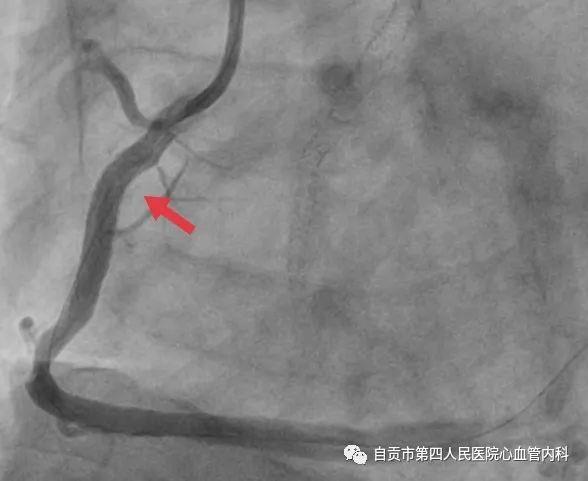

作者:汤勇 自贡市第四人民医院心血管内科引进又一利器“冠脉内超声检查(IVUS)”,助力冠心病精准治疗,目前我国冠心病发病率呈现一个高发的态势,冠心病的发病年龄也呈年轻化的趋势,20-30岁的人群发生急性心肌梗死也不少见。 ![]() 冠脉完全闭塞导致心梗 ![]() 急诊手术成功开通血管 药物加冠脉支架治疗是治疗冠心病的常规治疗手段,我们通常选择冠脉造影对患者的冠状动脉血管检查,由于冠脉造影显示的血管图像是二维图像,并不能完全真实地反映患者冠脉病变的实际情况,有可能造成不必要的支架植入,判断支架的大小完全依赖经验与造影图像,也有可能造成支架大小,长度选择不当。 ![]() ![]() 为了更精准对冠心病患者治疗,优化支架植入,减少支架植入的并发症的发生。 ![]() IVUS图像 ![]() 造影显示需要支架治疗 我院引进了美国波科公司的冠脉内超声检查(IVUS)检查设备,对患者的冠状动脉进行实时检查,为临床医生在对冠心病患者是否需要支架治疗,支架合理应用提供更为准确得信息。 ![]() 我们有一位患者在西昌某院因心肌梗死,行右冠状动脉支架治疗,当时冠脉造影检查提示右冠状动脉支架有一重度狭窄,建议择期再行支架治疗,患者慕名来我院来进一步检查。从冠脉造影的情况确实需要进行支架治疗,由于患者年轻,已安置支架4枚,故决定对患者进行冠脉内超声检查(IVUS)检查。 ![]() 支架局部膨胀不全 ![]() 冠脉内超声检查(IVUS) ![]() 支架直径恢复正常 患者冠脉内超声结果提示管腔面积能够满足心肌血供,且病变邻近血管直径大于5mm,不适合支架治疗。故建议其药物治疗,必要时复查造影。另外该患者造影显示已安置的支架显示膨胀不全的可能,进行冠脉内超声检查后显示支架内有明显膨胀不全的征象,故予以球囊扩张,支架管腔直径恢复正常。 在今后的冠心病治疗上,冠脉超声检查将发挥更大的作用,特别是复杂病变,左主干病变,钙化病变,闭塞病变方面,将大大减少冠脉介入治疗的并发症,再次支架治疗的发生率降低,将大大提高我院冠心病的精准治疗水平。 ![]() ![]() |